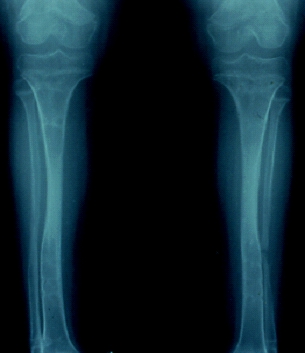

術前所見